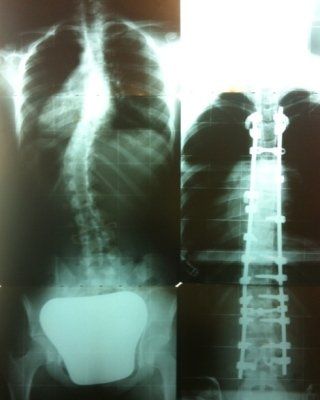

Trattamento Della Scoliosi Bari Dottor Andrea Piazzolla

Scoliosi Cause Cure Ed Esercizio Fisico